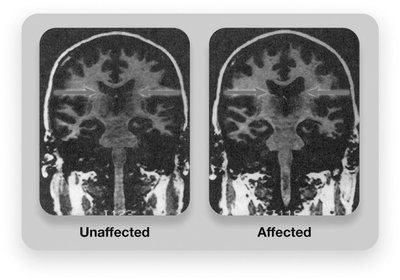

Brain Structure: Larger ventricles, loss of brain tissue, differences in hippocampus and amygdala.

Brain Activity: Reduced activity in frontal lobes and emotion/memory regions.